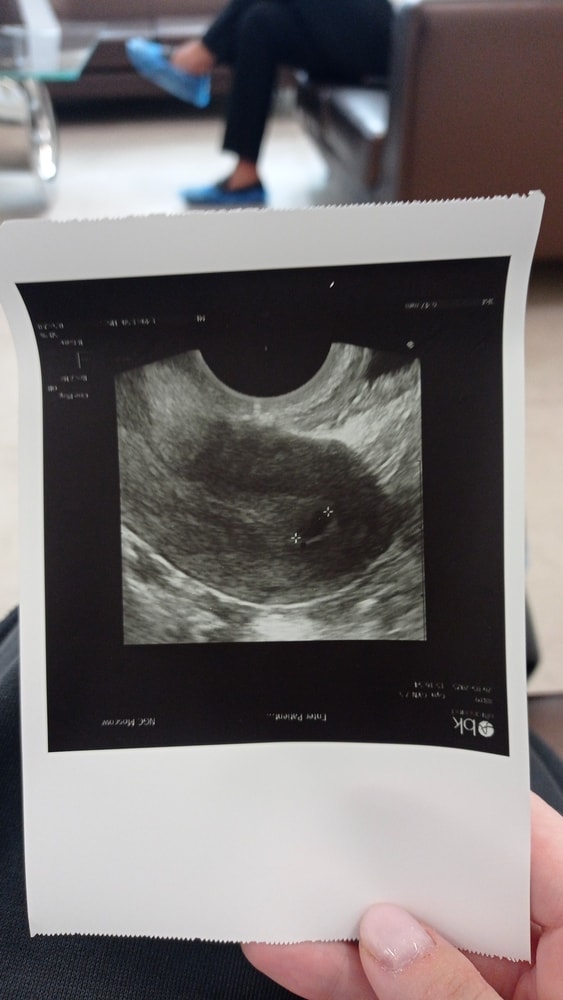

Всем здравствуйте! Я уже писала здесь. Была инсеминация, тест отрицательный, ХГЧ тоже. Начались месячные, они прошли 3 дня совсем не обильно, сегодня 4й день и нет ничего. Пошла сегодня к репродуктологу, она посмотрела и говорит похоже на плодное яйцо или кисту. Отправила сдать тест, он по-прежнему отрицательный. Завтра назначила сдать ещё ХГЧ. Может кто сталкивался с подобным.

Фото УЗИ в комментариях приложила.